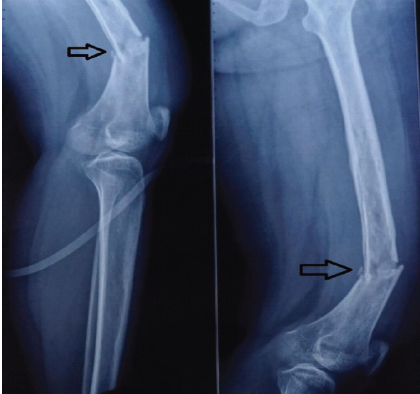

Fracture Occurrence following Prophylactic Nailing in a Case of Bisphosphonate-induced Atypical Femoral Fracture – A Rare Case Report

Kumardev Arvind Rajamanya , Tushar Nayak , Rahul Shah

………………………………p.116-120